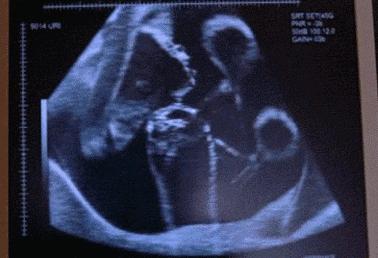

动图